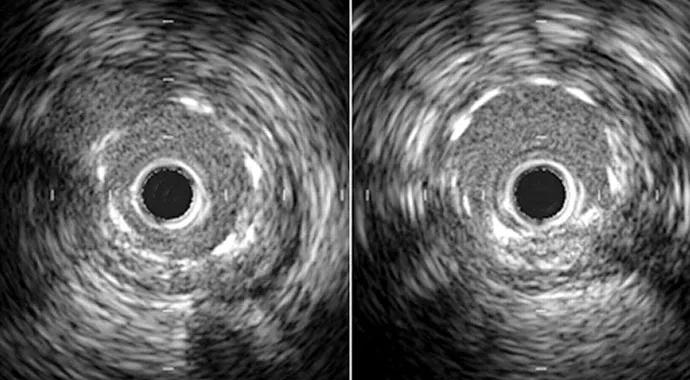

In contrast to FFR, IVUS facilitates assessment of blood vessel morphology. The cross-sectional views provided by IVUS clearly delineate the structure of an artery wall and diameter of the lumen. We often use IVUS to better visualize arterial segments not well seen on angiography, such as near overlapping branches or branching points.